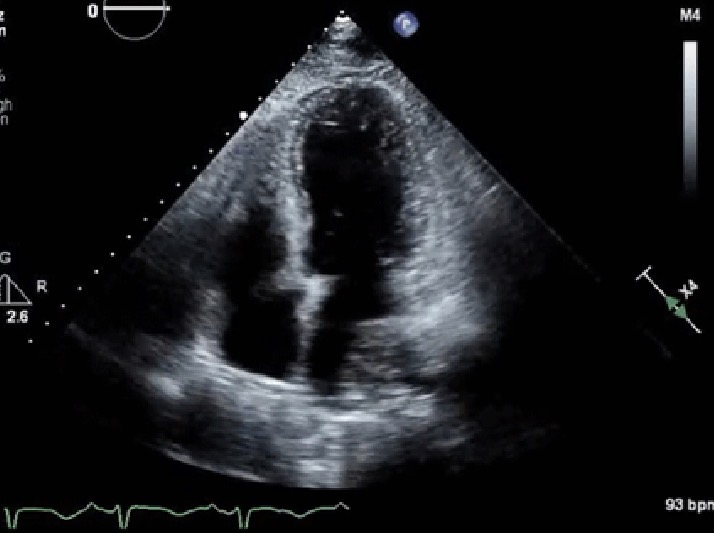

LV Noncompaction

What pathology does this echo look like?

Genetic cardiomyopathy with decreased coronary flow, thickened and trabeculated myocardium

Heart failure, embolism events, arrhythmia

List 3 clinical presentations of LV Noncompaction